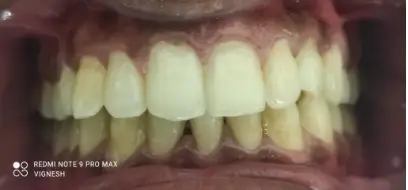

Case 1:

Result 1 Result 1

A young professional embarrassed by large visible gaps and forwardly placed teeth, showed up to get Illusion Aligners. The dentist then created a perfectly aligned and natural smile. The results were life changing. The patient reported improved self confidence with no hesitation in professional settings.